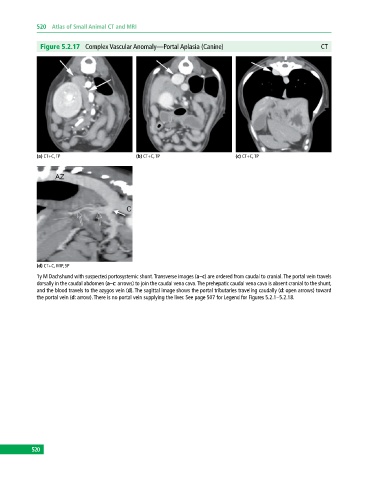

Figure 5.2.17 Complex Vascular Anomaly—Portal Aplasia (Canine) CT

(a) CT+C, TP (b) CT+C, TP (c) CT+C, TP

(d) CT+C, MIP, SP

1y M Dachshund with suspected portosystemic shunt. Transverse images (a–c) are ordered from caudal to cranial. The portal vein travels

dorsally in the caudal abdomen (a–c: arrows) to join the caudal vena cava. The prehepatic caudal vena cava is absent cranial to the shunt,

and the blood travels to the azygos vein (d). The sagittal image shows the portal tributaries traveling caudally (d: open arrows) toward

the portal vein (d: arrow). There is no portal vein supplying the liver. See page 507 for Legend for Figures 5.2.1–5.2.18.